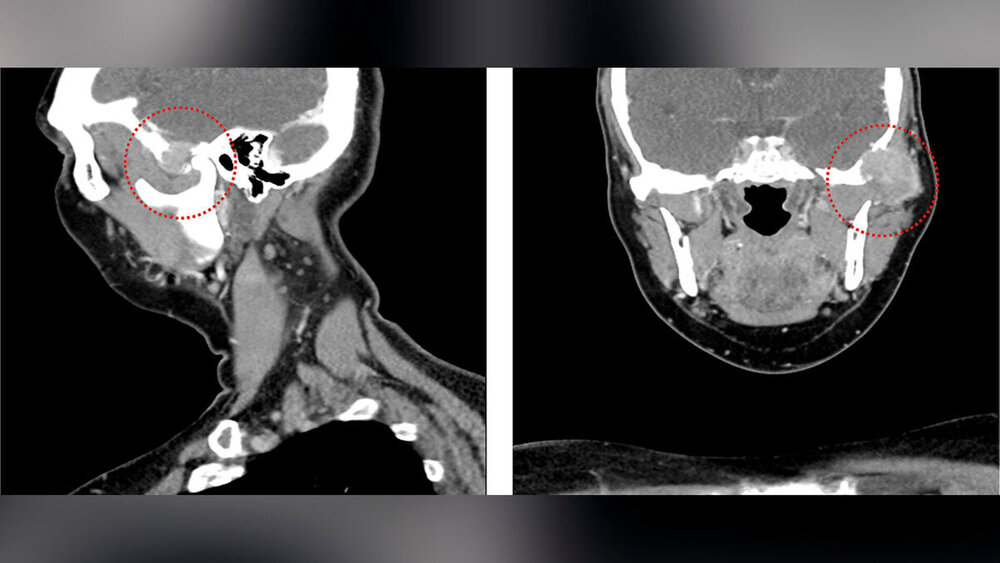

In der durchgeführten CT-Untersuchung mit Kontrastmittel (Abbildung 1) zeigte sich in der linken Gelenkpfanne des Kiefergelenks ein unscharf und destruierend wachsender Tumor mit einem maximalen Durchmesser von etwa 3 cm. Der Tumor arrodierte das Felsenbein und einzelne Mastoidzellen. Die knöcherne Begrenzung der mittleren Schädelgrube zeigte sich nach intrakraniell aufgehoben und die Dura mater zum angrenzenden Temporallappen wurde bereits nach medial verdrängt. Der linke Jochbogen zeigte sich ebenfalls knöchern destruiert, das linke Kiefergelenkköpfchen war jedoch intakt. Im MRT zeigten sich neben einer Tumorinvasion des Musculus temporalis auch ipsilateral links intra- und paraparotideale Lymphknoten, die im Seitenvergleich vermehrt imponierten (Größe < 1 cm). Im Level IIb links zeigten sich im Seitenvergleich ebenfalls vermehrt Lymphknoten, allerdings ohne einen konkreten morphologischen Malignitätsverdacht.